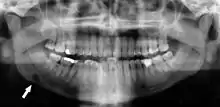

Stafne's defect is usually discovered by chance during routine dental radiography.[4] Radiographically, it is a well-circumscribed, monolocular, round, radiolucent defect, 1–3 cm in size, usually between the inferior alveolar nerve (IAN) and the inferior border of the posterior mandible between the molars and the angle of the jaw. It is one of the few radiolucent lesions that can occur below the IAN. The border is well corticated and it will have no effect on the surrounding structures. Computed tomography (CT) will show a shallow defect through the medial cortex of the mandible with a corticated rim and no soft tissue abnormalities, with the exception of a portion of the submandibular gland. Neoplasms, such as metastatic squamous cell carcinoma to the submandibular lymph nodes or a salivary gland tumour, could create a similar appearance but rarely have such well defined borders and can usually be palpated in the floor of the mouth or submandibular triangle of the neck as a hard mass. CT and clinical exam is typically sufficient to distinguish between this and a Stafne defect. The Stafne defect also tends to not increase in size or change in radiographic appearance over time (hence the term "static bone cyst"), and this can be used to help confirm the diagnosis.[4] Tissue biopsy is not usually indicated, but if carried out, the histopathologic appearance is usually normal salivary gland tissue. Sometimes attempted biopsy of Stafne defects reveals an empty cavity (possibly because the gland was displaced at the time of biopsy), or other contents such as blood vessels, fat, lymphoid or connective tissues. Defects of the anterior lingual mandible may require biopsy for correct diagnosis at this unusual location.[2] The radiolucent defect here may be superimposed on the lower anterior teeth and be mistaken for an odontogenic lesion. Sometimes the defect may interrupt the contour of the lower border of the mandible, and may be palpable. Sialography may be sometimes used to help demonstrate the salivary gland tissue within the bone.